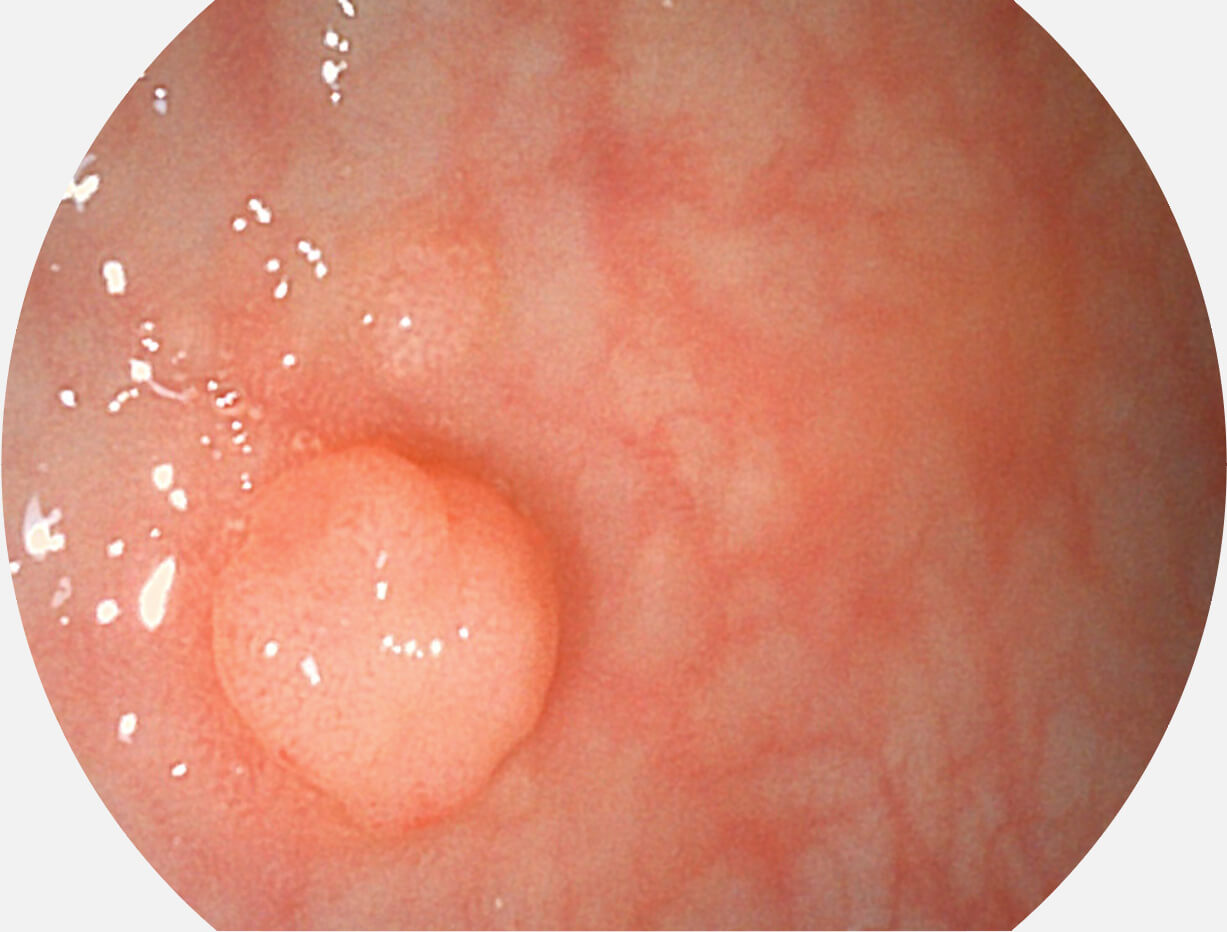

图像具有高亮度、高黏膜血管颜色对比度的特点,且不改变粘液、食物残渣、粪便的基本颜色,可在中远景下进行观察,助力消化道早期疾病的诊断。

采用光路合束技术,光谱自由度高,实现了更丰富的照明模式,染色模式SFI及VIST,从远景到近景,助力消化道早期疾病诊断。